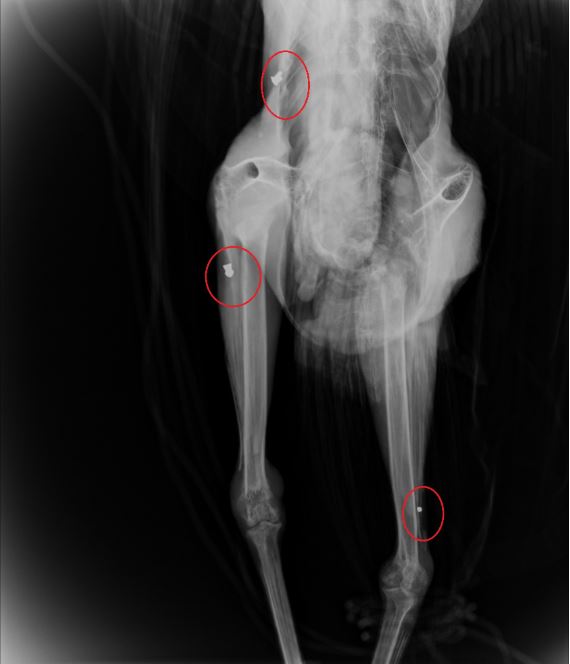

Το παγώνι φέρεται να δέχθηκε πυροβολισμούς, γεγονός που επιβεβαίωσαν και σχετικές ακτινογραφίες που «έδειξαν» μάλιστα δυο βολίδες αεροβόλου κι ένα σκάγι.

«Το ζώο αυτό έχει πυροβοληθεί τρεις φορές, την ίδια ώρα ή διαφορετικές δεν μπορούμε να ξέρουμε, ούτε αν ο δράστης είναι ένας ή δύο ή τρεις, μέσα ή δίπλα σ’ έναν από τους πιο πολυσύχναστους αρχαιολογικούς χώρους της Κρήτης και της Ελλάδας γενικότερα» αναφέρει χαρακτηριστικά σε ανάρτηση του ο Σύλλογος ΑΝΙΜΑ.